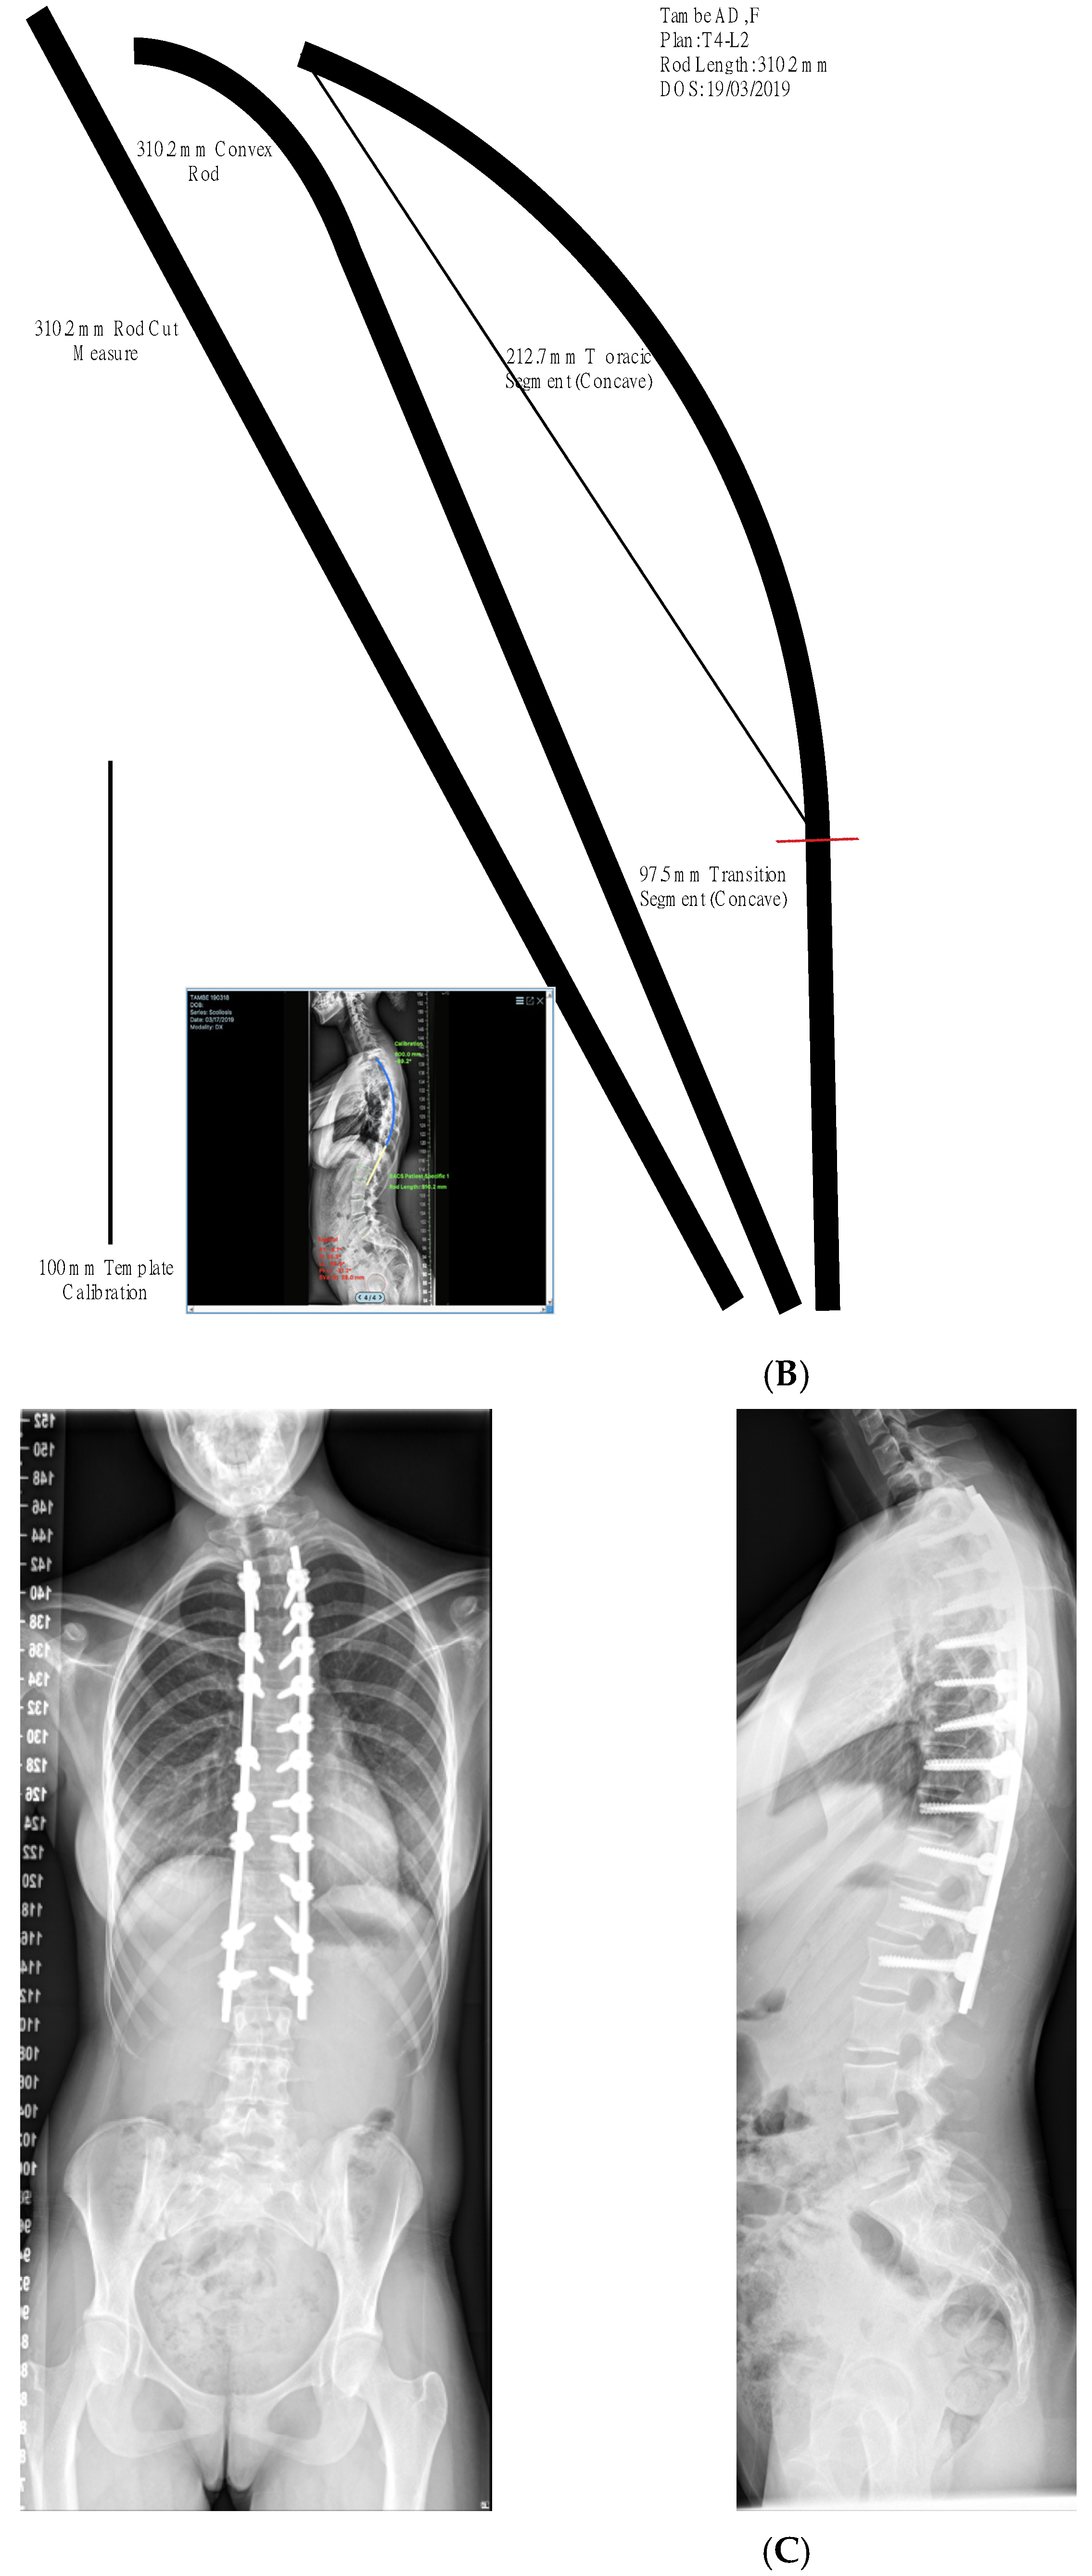

2. Materials and Methods